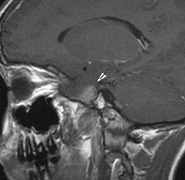

Intracranial leptomeningeal capillary vascular malformation (Figs. 21 and 22) is associated with seizures and contralateral neuromuscular weakness. Central nervous system involvement correlates highly with ipsilateral involvement of the V1 dermatome by a PWS.208,218

Fig. 22. Axial T2-weighted (a) and coronal T1-weighted (b) images of a 16-year-old boy with a port-wine lesion over the right side of his face. The right hemisphere is markedly atrophic and abnormal draining veins are seen within the right lateral ventricle (arrowheads). (c, d) The entire right hemisphere is covered by an enhancing pial angioma and the choroid plexi are enlarged. Enhancing retinal angiomas (arrows), typical of Sturge-Weber syndrome, are seen in (d).

It has been hypothesized that the calcific changes reflect cellular anoxic injury secondary to venous stasis/poor drainage.219,220 Abnormal autonomic innervation has also been reported in association with the malformed cortical vessels—innervation only by noradrenergic fibers.221 Studies suggest that the normal increase in brain-blood flow to accommodate increased metabolic demand during seizure activity is blunted in affected brain regions of SWS.222 Thus, seizures in the setting of impaired perfusion may be exacerbating brain injury. Periods of contralateral weakness (days to weeks) can follow a prolonged seizure episode.206,223